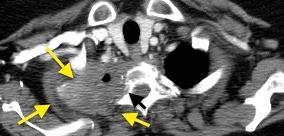

Hematoma pleural después de cateterismo.

Rotura de aneurisma de arteria subclavia Aneurisma “deshinchado” Hemotórax

Fallece en el acto de tomar esta radiografía. La mayoría ateroescleróticos. Más frecuente a la derecha.La rotura: 32-47% de las muertes.

Sun J et al. Isolated True Subclavian Aneurysm without Aberrant Subclavian Artery or Coarctation of Descending Aorta. Annals of Vascular Surgery 2021